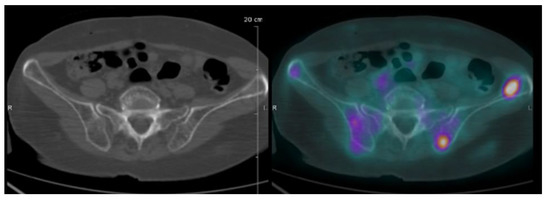

| Focal lesion | Foci of uptake above the surrounding background noise on two successive sections with or without osteolysis on the CT image | Suggested as pejorative prognostic biomarker using cut off 3. | Bartel et al., 2009 [8] |

| EMD | Tissue invasion without contiguous bone involvement. | Presence of EMD suggested as pejorative prognostic biomarker | Zamagni et al., 2011 [9] |

| PMD | Soft tissue invasion with contiguous bone involvement. | Presence of PMD suggested as pejorative prognostic biomarker | Moreau et al., 2019 [19] |

| Diffuse medullary involvement | Homogenous diffuse uptake of the pelvic-spinal-peripheral skeleton higher than the liver background. | Prognostic value currently not demonstrated | |

| FDG-PET/CT abnormality | Presence of Focal lesion(s) and/or EMD lesion(s) and/or PMD lesion(s) and/or diffuse medullary involvement. | Absence of FDG-PET/CT abnormality considered as a favourable prognostic | Rasche et al., 2017 [16] |